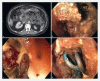

Background and study aims Endoscopic drainage of walled-off necrosis and subsequent endoscopic necrosectomy has been shown to be an effective step-up management strategy in patients with acute necrotizing pancreatitis. One of the limitations of this endoscopic approach however, is the lack of dedicated and effective instruments to remove necrotic tissue. We aimed to evaluate the technical feasibility, safety, and clinical outcome of the EndoRotor, a novel automated mechanical endoscopic tissue resection tool, in patients with necrotizing pancreatitis. Methods Patients with infected necrotizing pancreatitis in need of endoscopic necrosectomy after initial cystogastroscopy, were treated using the EndoRotor. Procedures were performed under conscious or propofol sedation by six experienced endoscopists. Technical feasibility, safety, and clinical outcomes were evaluated and scored. Operator experience was assessed by a short questionnaire. Results Twelve patients with a median age of 60.6 years, underwent a total of 27 procedures for removal of infected pancreatic necrosis using the EndoRotor. Of these, nine patients were treated de novo. Three patients had already undergone unsuccessful endoscopic necrosectomy procedures using conventional tools. The mean size of the walled-off cavities was 117.5 ± 51.9 mm. An average of two procedures (range 1 - 7) per patient was required to achieve complete removal of necrotic tissue with the EndoRotor. No procedure-related adverse events occurred. Endoscopists deemed the device to be easy to use and effective for safe and controlled removal of the necrosis. Conclusions Initial experience with the EndoRotor suggests that this device can safely, rapidly, and effectively remove necrotic tissue in patients with (infected) walled-off pancreatic necrosis.